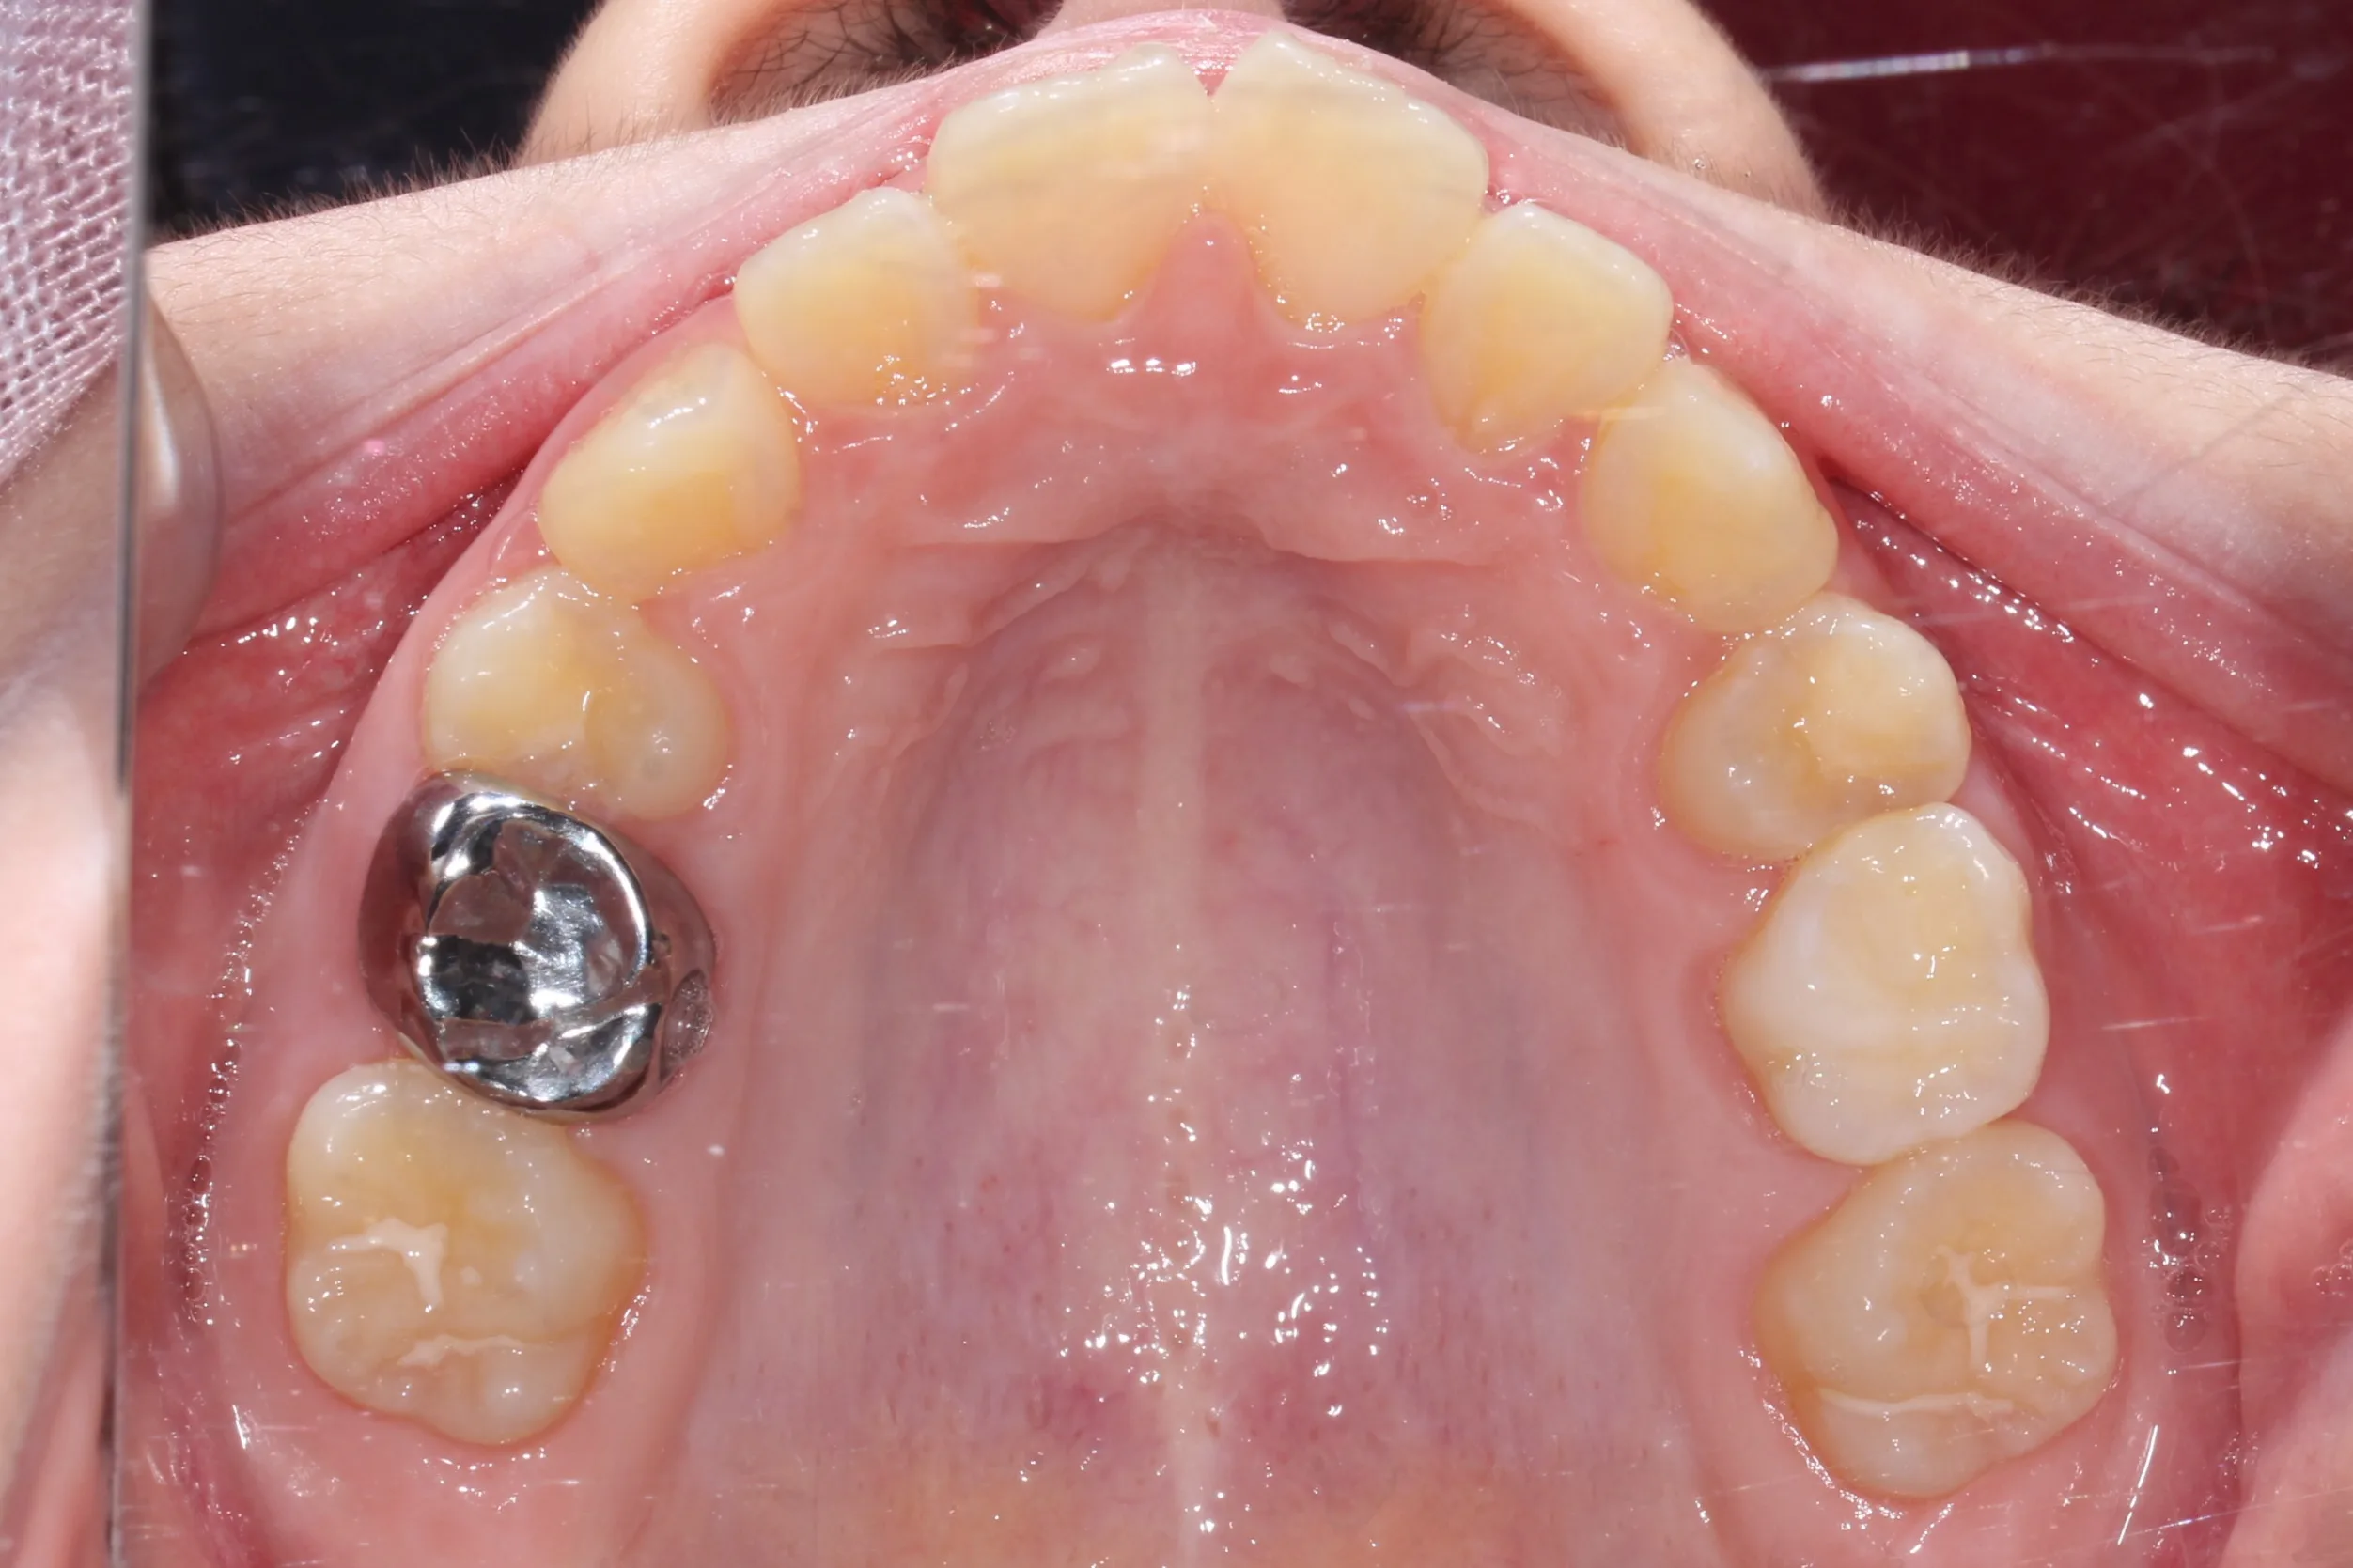

만 11세 환자분께서 튀어나온 앞니와 다물어지지 않는 입술 때문에 내원하셨습니다. 검진 결과 상악 전돌을 동반한 2급 부정교합(Class II malocclusion) 상태였으며, 아래턱의 성장이 다소 부족하여 골격적인 조화가 필요한 상황이었습니다.

이번 치료에는 인비절라인 퍼스트(Invisalign First)에 하악 전방 견인(Mandibular Advancement, MA wing)을 추가하여 치료를 진행하였습니다. 성장기라는 시기적 특성을 적극 활용하여 아래턱의 점진적인 성장을 유도하고, 과도한 상악 전치부 돌출을 개선하는 데 치료의 핵심 전략을 두었습니다.

2년 7개월의 치료 과정을 거치며 환자분의 협조도 덕분에 안모 프로파일과 교합이 안정적으로 개선되었습니다. 성장기라고 해서 무조건 교정이 어려운 것은 아닙니다. 적절한 시기에 맞춤형 장치를 선택한다면 골격적 불균형을 효과적으로 바로잡을 수 있습니다.